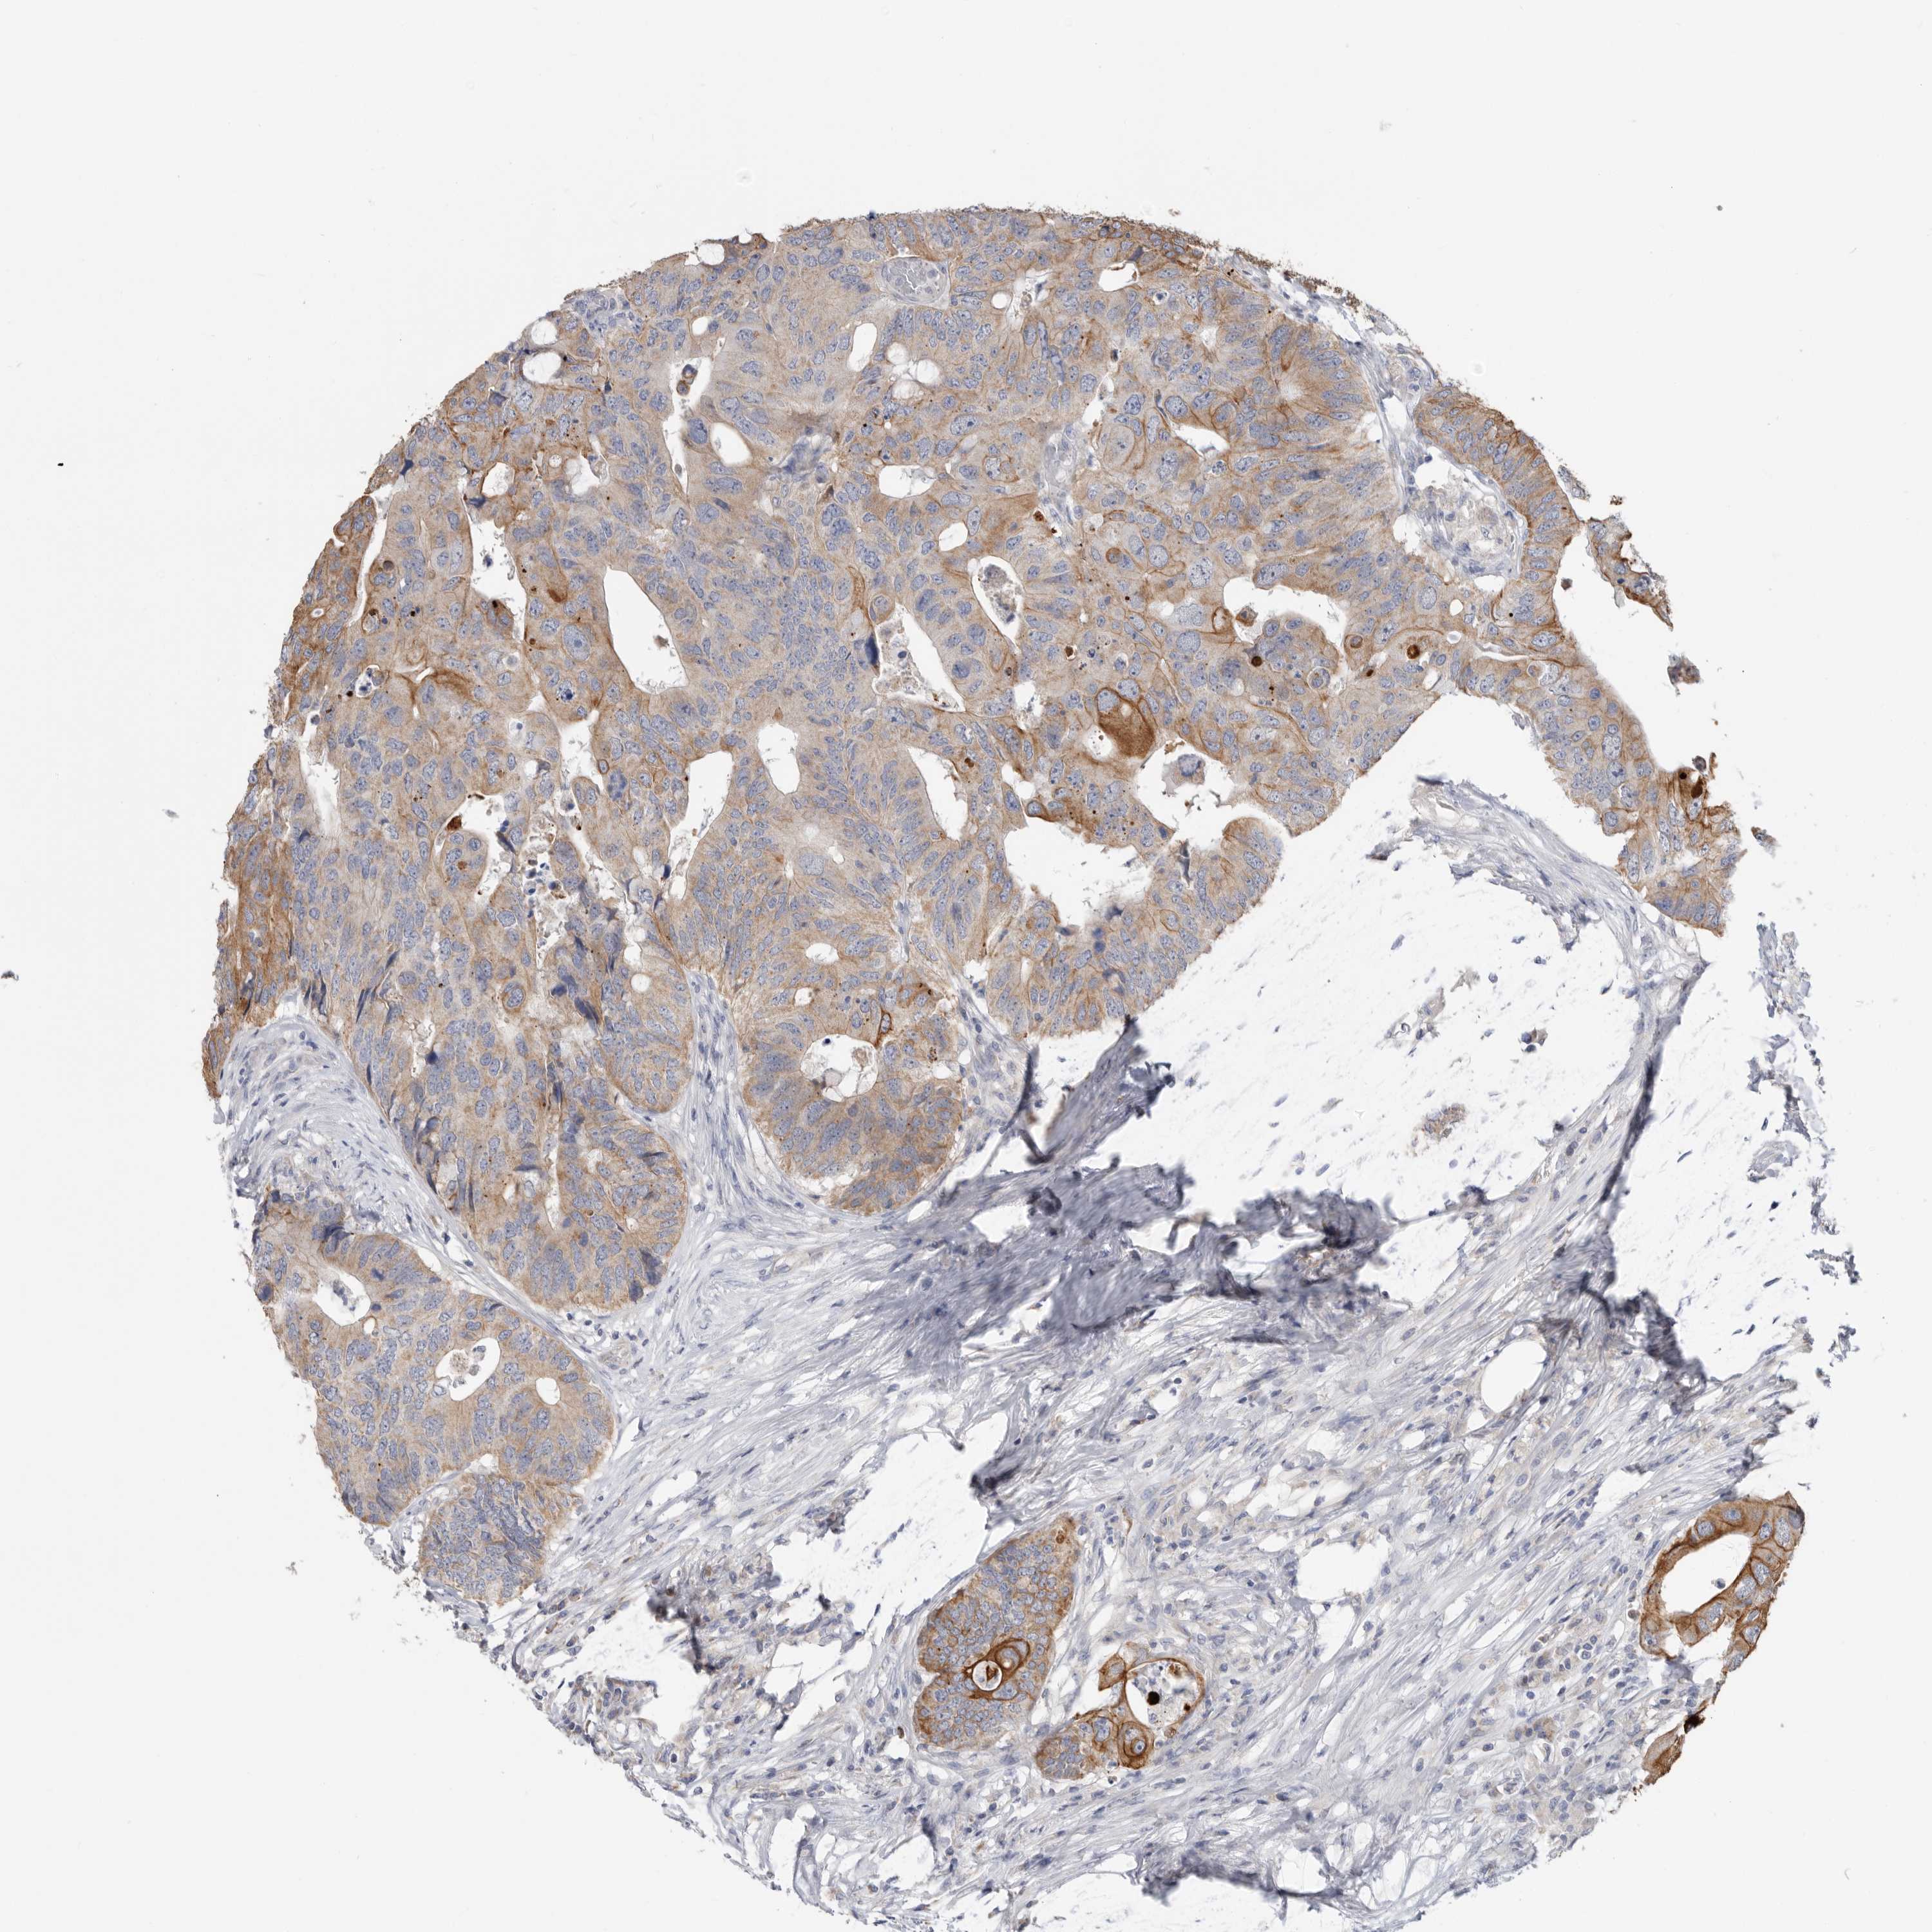

CANCER COLORECTAL CANCER Show tissue menu

Colorectal cancer

Human cancer

Colon adenocarcinoma